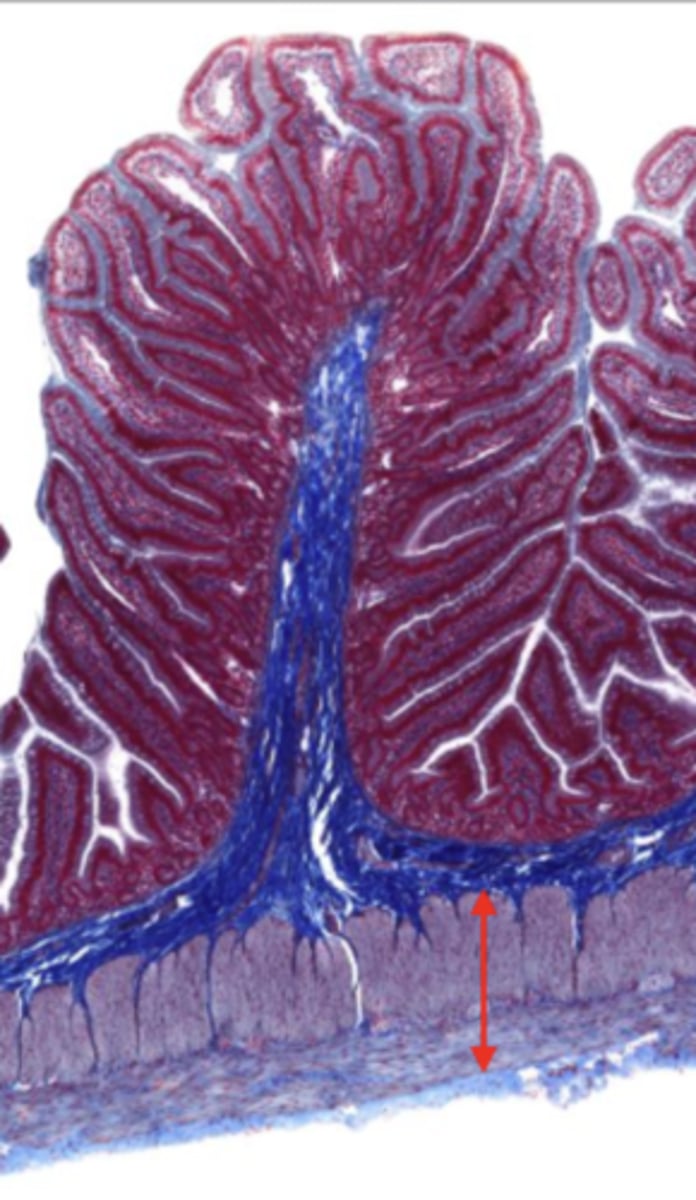

jejunum (histology)

simple columnar epithelium

villi (jejunum)

intestinal crypts (jejunum)

lumen (jejunum)

mucosa (jejunum)

mucosal epithelium (jejunum)

lamina propria (jejunum)

muscularis mucosa (jejunum)

submucosa (jejunum)

contains glands and blood supply

muscularis externa (jejunum)

serosa/adventitia (jejunum)